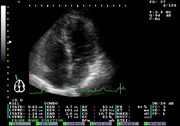

| 心臓の壁の厚さや壁運動異常の有無、心機能の評価を行います。また、ドプラー法により弁の血流状態や逆流の有無もわかります。高血圧症、狭心症、弁膜異常や心不全等の心機能評価に有用です。 |

| 心機能の評価 |